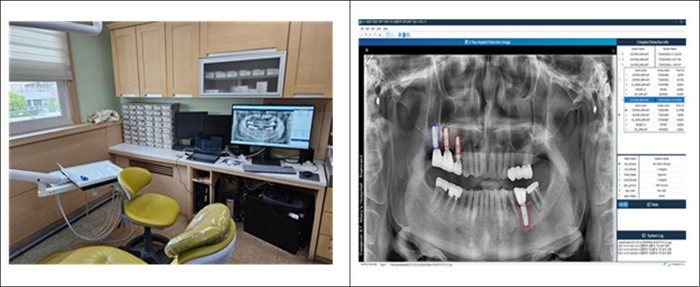

의료 현장에 적용한 실증 기술은 '치과 의료현장을 위한 AI기술이 적용된 임플란트 판독 분류솔루션'이다.

의료진이 빠르고 쉽게 임플란트 제조사와 제품명을 찾아주는 지원 서비스다. 국내외에서 유사 서비스가 존재하지만 대부분 제한적 서비스 형태로 제공되며 임플란트 데이터베이스가 충분하지 않은 단점을 갖고 있다.

한국플랫폼서비스기술 제품은 국내외에 출시된 다양한 임플란트 데이터베이스를 제공하고 검색이 가능한 10만개 이상 X-레이 이미지데이터와 3만개 이상 특징 분류가 가능한 학습데이터를 보유했다. AI기술이 적용된 자동 식별 및 판독 분류지원 기능을 탑재한 병원용 의료서비스도 개발해 지역 대학병원과 실증하고 있다.

솔루션이 의료 현장에 보급되면 시술된 임플란트 모델의 정확한 식별과 세부 정보 파악이 훨씬 빠르고 정확하게 진행될 수 있다. 정확한 정보 제공으로 환자의 심적, 경제적 고통을 덜어주고 의료진의 안전한 시술에도 도움이 될 전망이다.